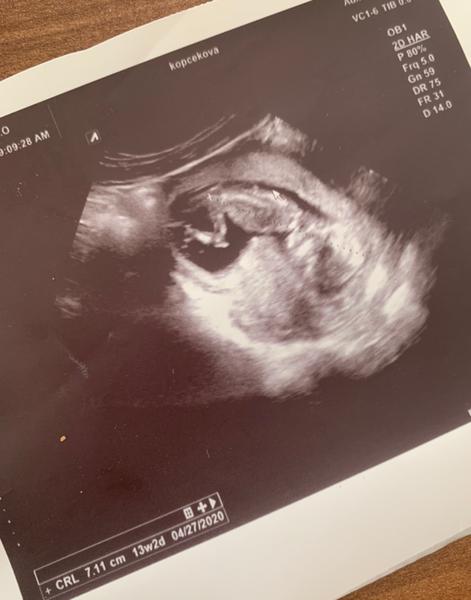

dnes som bola na ultrazvuku a odvtedy mám paniku, že sa mi tam bábo nezmestí. Mám pocit akoby sa tam nezmestilo a je tam zapichnuté a stlačené.

Doktor nevravel nič a ani som si to neuvedomila. Až teraz, keď sa pozerám na snímok a porovnávam snímky iných mamičiek, tak mi to to prišlo, že to nie je v poriadku.

ak Vám lekár nič nepovedal, tak je všetko v poriadku. Plod svojou veľkosťou zodpovedá 13. týždňu.

Môže ísť len o iné priloženie ultrazvukové sondy.